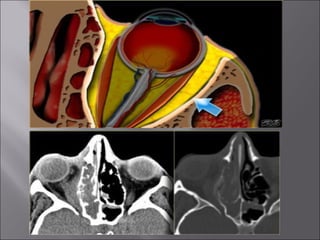

Ultrasound and CT scans provide anatomical images of the orbit, while color Doppler imaging provides visualizations of vascular structures and blood flow within lesions. These imaging techniques are used to evaluate a variety of orbital conditions involving blood vessels, infections, tumors, congenital issues, trauma, and more, and can help identify vascular disorders, thrombosis, treatment responses, and dynamic changes in benign tumors over time.